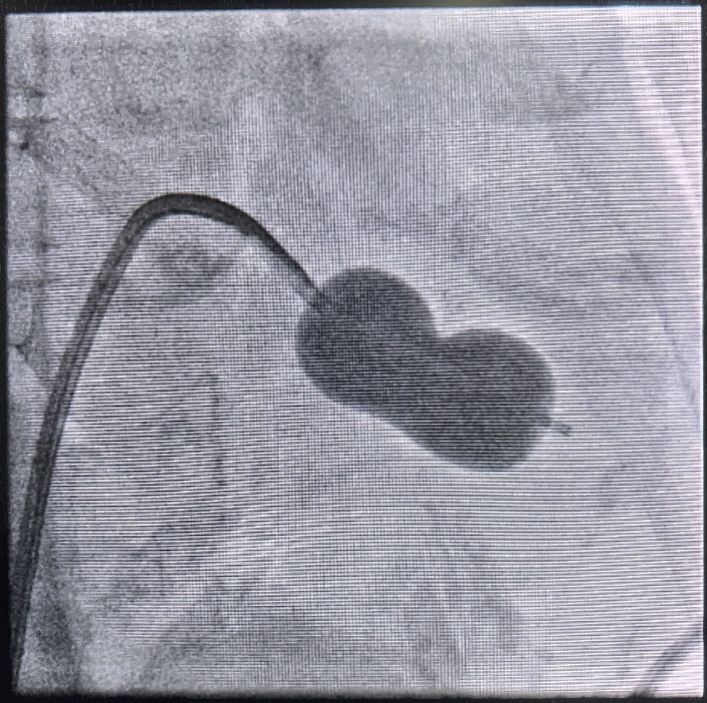

球囊扩张术中影像

术后复查超声心动图结果更是印证了手术的显著效果:术前超声测得二尖瓣流速250cm/s,平均跨瓣压差11mmHg,反流面积15cm²;术后复查显示,二尖瓣血流速度降至155cm/s,平均跨瓣压差降至6mmHg,反流面积缩小至13cm²,各项指标均较术前明显改善,达到了预期的治疗效果。